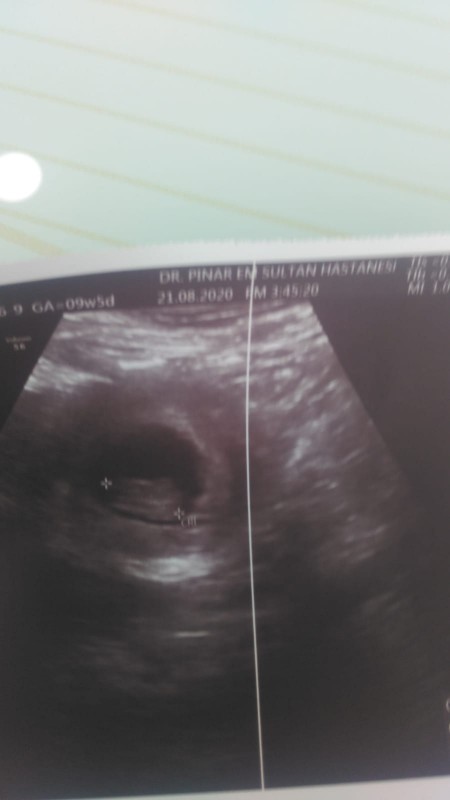

24 Ağustos 2020 Hamilelik Dönemi Genel kategorisinde (27 puan) sordu

Kızlar ablam adına soruyorum.ramiz nub teorisinden anlayan tahmin edebilir mi?çok teşekkürler

Kapatılma nedeni: Cinsiyet tahminlerini sol.üst köşeden sohbet bölümünden sorabilirsiniz